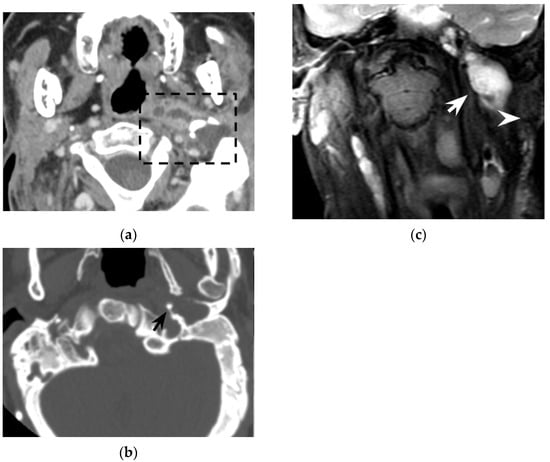

Figure 4. Eighty-seven-year-old man with history of external mycotic otitis. T2w MRI in axial (a) and coronal (c) planes show abnormal right mastoid (dotted rectangle) filled with hyperintense material that spreads into the neck (white arrows). Axial (b) and coronal (d) bone CT images show opacified right mastoid, absence of bone trabeculae, and a wide defect (black arrows) at the mastoid tip. Images were consistent with an infected cholesteatoma eroding the mastoid tip and spreading into the neck. The finding was confirmed at surgery.